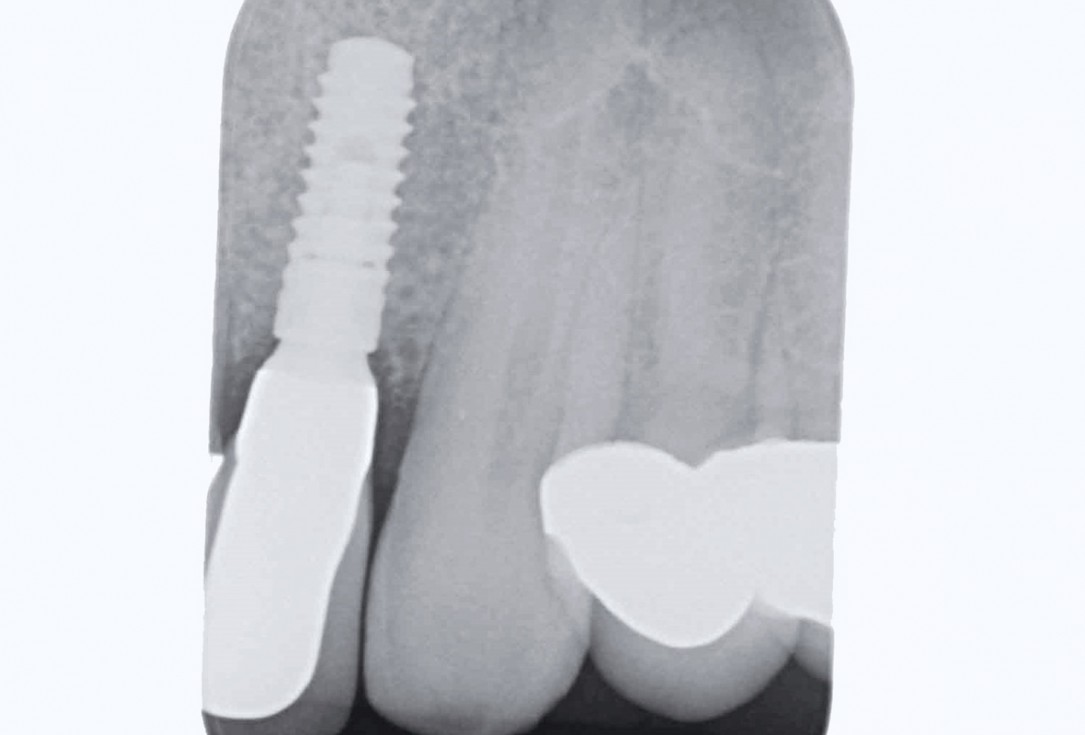

2/19 - Initial situation: x-rayBone augementation with maxresorb® - Dr. R. Cutts